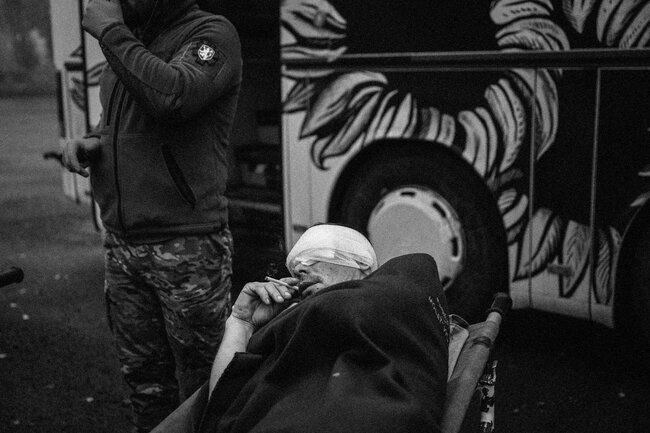

Мы в «Австрийке», эвакуационном автобусе добровольческого батальона «Госпитальеры». За рейс он может перевезти шесть тяжелораненых и пару десятков легких. Сейчас мы отправим их из сельской больнички в больницы Днепра, это третье плечо эвакуации.

Первое — когда солдаты вручную тащат раненого до точки эвакуации — места, куда может подъехать транспорт. Как правило, это что-то бронированное, что может вывезти человека до стабпункта — какого-нибудь подвала в десяти километрах от нуля [передовой] или в сельскую больничку, где боевые медики пытаются стабилизировать раненого и обезболить. Это «кейсэвак», второе плечо. Если жизнь раненого спасена, его транспортируют в серьезную больницу, это «медэвак».

«Австрийка» — одна из бесчисленных эвакуационных машин, мотающихся по дорогам Донбасса, от остальных отличается только размером: она самая большая, восемь человек экипажа.

Ходячие раненые зябко ковыляют от дверей больнички и набиваются в автобус. У каждого в руках — «форма 100», подслеповатый листочек бумаги с информацией о ранении. Они выглядят потерянно, как жертвы кораблекрушения. Командир экипажа уверенным голосом помогает им сориентироваться: «Так, друзья, буду называть фамилии, если ошибусь в ударении, извините. Поднимайтесь на борт, садитесь, куда удобно. Девчата, там сзади есть места?.. Буряк?» — «Я…» — «Лисовский?» — «Я…» — «Гончарук?» — «Я…» — «Данилов?» — «Я…» — «„Сотки“ у всех на руках? Хлопцы, трамбуемся!» В заднюю дверь подъемником загружают лежачих, в основном с оторванными ногами.

— Это салон для курящих? — парень с раздробленными ногами с трудом улыбается, тут же закрывает глаза и отключается снова. Потом я вижу его в приемном покое больницы. Вместе с пожилой санитаркой мы берем его каталку и везем в отделение.